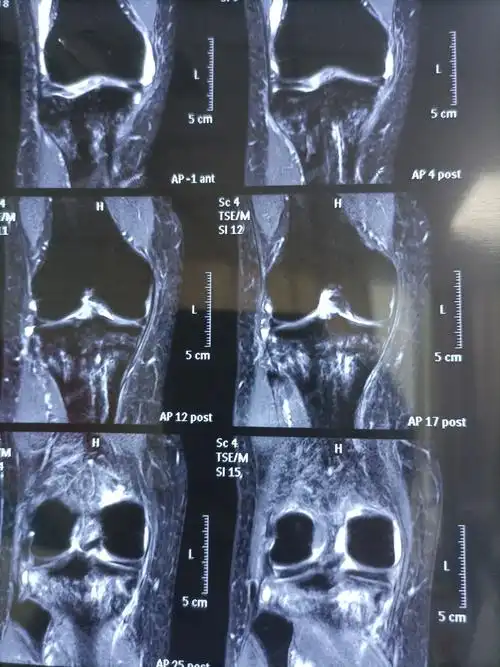

膝关节磁共振显示膝关节前交叉韧带断裂

矢状位显示:前交叉韧带断裂

核磁共振提示前交叉韧带完全断裂.